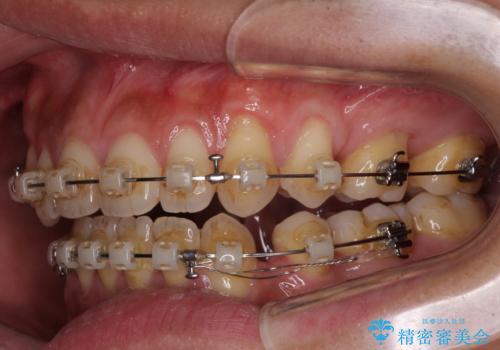

- クリアブラケット

- 2年6ヶ月

- 上下前歯の隙間と口元の出っ張った感じを気にして来院された患者様です。

上下の隙間は舌突出癖によるもので、またその癖により前歯が前方に出ている状態でした。

口元の出っ張りを改善するため、上下左右第一小臼歯4本を抜去し、ワイヤー装置にて矯正治療を行うこととしました。